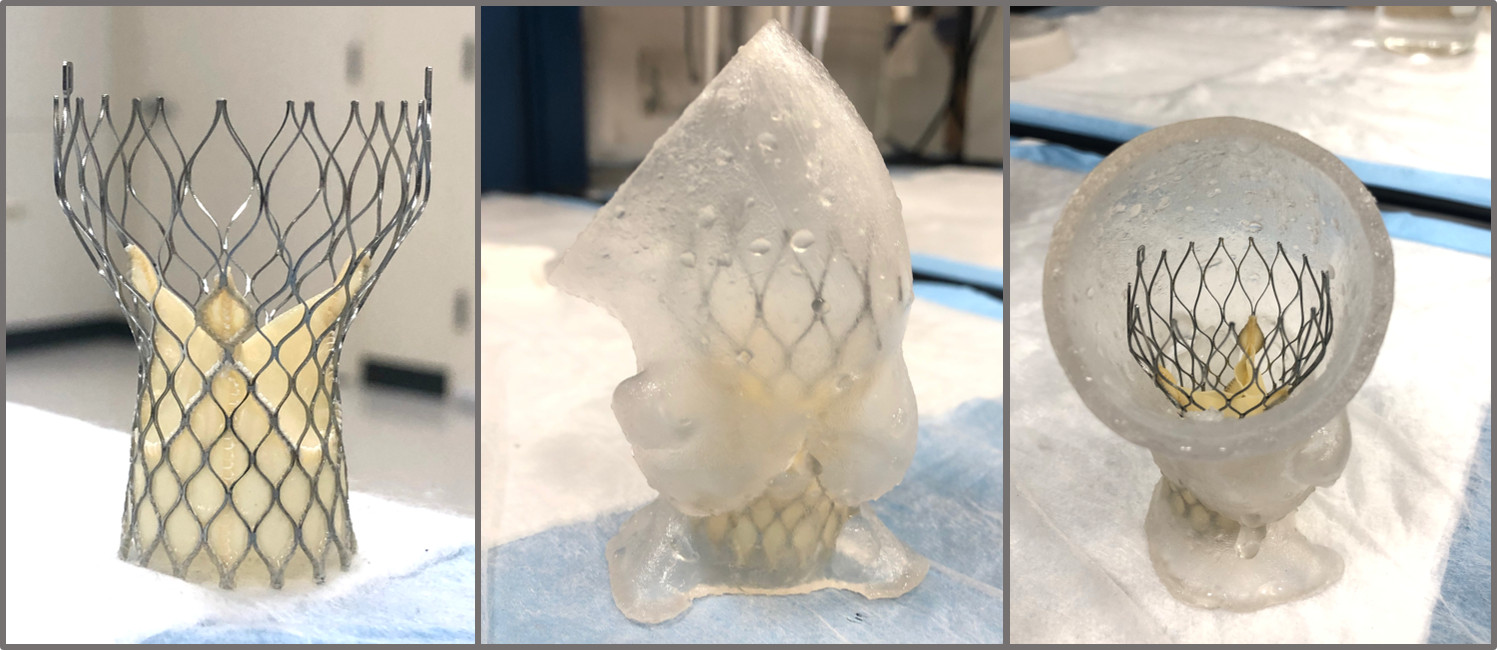

The goal of this research was to develop a patient-specific replica of calcific aortic

valve disease(CAVD) to emulate the expected clincial performance of the TAVR devices.

In collaboration with Vascular Simulations, we developed such a model to interface with the advanced simulation system called

the Replicator Pro, which allows us to study various patient anatomies inside the

cath-lab as if it was a patient on the table. We can rapidly deploy, measure and image

the valves for clinical evaluations as well as develop more adavanced imaging techniques

such as an intra-procedural CT for measure the coaption of the stent to the replica

lumen.

Two different TAVR devices, one self-expandable polymeric and one balloon-expandable tissue valve, were evaluated according to the ISO 5840 guidelines but in five different patient models. The patient-specfic results were compared to the idealized geometry simulator commonly used in ISO 5840 testing, and we showed that the current standards can dramitically overestimate the performance of the valves.